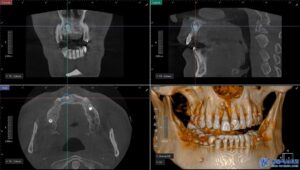

진단 결과, 문제의 치아는 위 앞니 중에서도

정중앙에 위치한 오른쪽 큰 앞니로,

치아 상태도 많이 나빠져 있었고

만성 치주염으로 인해 치근 끝에

염증이 크게 퍼져 흔들림이 있는 상태였습니다.

결국, 해당 치아는 살릴 수 없는 상태였기에

발치를 진행하기로 하였으며,

치근낭(치아 뿌리 주변에 형성된 염증 조직)도

함께 제거하고 염증으로 잇몸뼈가 녹은 부위는

잇몸뼈를 이식하여 잇몸이

꺼져 보이지 않도록 진행하기로 하였습니다.